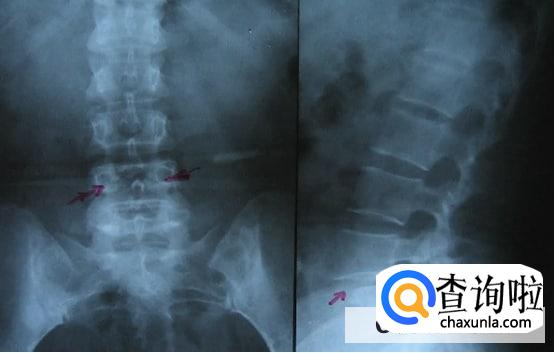

有部分小伙伴在睡觉的时候出现腰酸背痛是强直性脊柱炎,强直性脊柱炎其实会导致患者腰部出现不适,背部也会变得僵硬,一般在早期时就需要积极的配合医生治疗。

如果小伙伴们出现腰酸背痛的症状比较明显,并且伴随僵硬等等问题,这时候要及时的去医院通过查体和检查,从而排除身体是否出现其他的疾病。